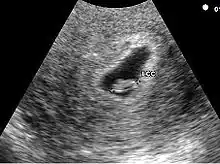

Embryon à 5 semaines

Embryon à 5 semaines. L'embryon est entre les deux croix. La structure arrondie au-dessus de l'embryon est la vésicule vitelline

L'embryon est visible dès 5 semaines en cas d'utilisation de sonde endovaginale de haute fréquence. Il se présente comme une zone hyperéchogène coincée entre la vésicule vitelline et la paroi du sac ovulaire. Une activité cardiaque peut être visualisée. Il est déconseillé, à ce stade, d'utiliser le doppler pour entendre l'activité cardiaque embryonnaire en raison d'effet délétère possible sur la formation du cœur. En raison de la sensibilité humaine au mouvement, il est parfois possible de visualiser une activité cardiaque avant la visualisation de l'embryon. En pratique, l'activité cardiaque doit être systématiquement vue dès que l'embryon mesure mm.